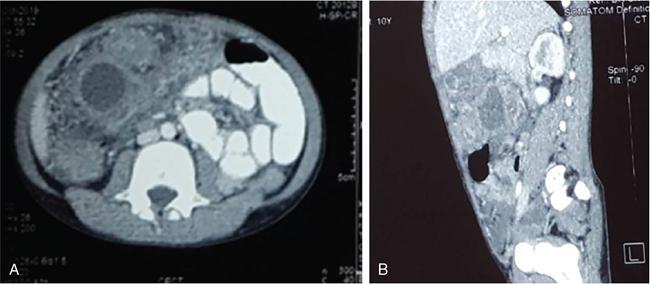

Rashmi Dixit, Anju Garg Abdominal masses are a common clinical problem in children, arising from virtually any abdominal organ. Masses arising from the gastrointestinal (GI) tract are not uncommon. They may be congenital or developmental, inflammatory, infective, idiopathic or neoplastic in nature. A high index of suspicion is necessary so as to ensure an early diagnosis and appropriate management. Imaging, therefore, plays a vital role in identifying the location, nature and extent of the mass lesion. Ultrasound (US) is the first-line imaging method for GI masses, like for most paediatric abdominal masses. It does not require sedation and is nonionizing which are important considerations in the paediatric population. US findings may be diagnostic in certain masses when no further imaging is required. Computed tomography (CT) plays an important role in complete evaluation of GI masses especially where US is either not diagnostic or the full extent and nature of the mass needs to be delineated, especially prior to surgery. It requires the administration of intravenous contrast and preferably oral contrast as well. Sedation may be required and it carries the risk of radiation exposure. Each study, hence, needs to be tailored to answer the clinical question at hand, while ensuring the lowest possible radiation exposure. Magnetic resonance imaging (MRI) provides excellent contrast resolution, which along with its nonionizing nature makes it a very attractive imaging technique. However, due to the relatively long imaging time requiring sedation, sensitivity to motion both respiratory and bowel and limited availability it is generally used as a problem-solving tool. Plain films and contrast studies currently have a very limited role in the evaluation of GI masses. Plain films may be diagnostic in masses like teratomas, while contrast studies may be required for mucosal abnormalities and small endoluminal masses like polyps. Enteric duplication cysts can occur along any portion of the GI tract from the pharynx to the rectum. They are found most often in the ileum (33%). The other sites are the oesophagus (20%), colon (13%), jejunum (10%), stomach (7%) and duodenum (5%). The incidence is reported to be around 0.2% of all children, with a slight male predominance. Duplication cysts are thought to arise between the 4th and 8th weeks of development; however, their aetiology is unknown and several different theories have been proposed. In 16%–26% cases there may be associated spinal defects, cardiac or urinary malformations. Other associated GI anomalies may be seen in about 10% of cases. Duplication cysts typically lie along the mesenteric border of the gut. They have smooth muscle wall which they share with the adjacent gut, as also the blood supply. On histopathology, three classical features are seen: an epithelial lining with GI mucosa, a smooth muscle covering and a close attachment to the GI tract due to a shared common wall. Although the mucosal lining does not necessarily match with the adjacent portion of the gut, nonetheless, duplications are named after the portion of the gut to which these are closely related. About 20%–30% of these duplication cysts contain ectopic gastric mucosa which is more common in oesophageal and small intestinal duplication cysts. Ectopic pancreatic mucosa may also be seen, most often in gastric duplication cysts. Morphologically they may be cystic or tubular with the former accounting for 80% and the latter for 20%. While cystic duplications mostly do not communicate with the adjacent gut, tubular duplications that run parallel to the GIT often do, hence in these cases connection with GIT must be demonstrated for operative planning. Duplication cysts may be multiple in 1%–7% of cases usually occurring in the same segment of the GIT. An atypical duplication cyst is an isolated duplication cyst which is completely separated from the GIT and has no communication or shared wall with the gut. They are extremely rare and thought to be the result of a vascular injury. Although duplication cysts may remain asymptomatic till adulthood they mostly present within the first year (70%). Almost 85% present by the second year. Clinical features depend not only on the size and location, but also on the presence of any ectopic mucosa and complications. Pharyngeal and oesophageal cysts may present with respiratory distress or dysphagia. Infection and rapid growth may cause retrosternal pain or haemoptysis. Gastric and intestinal duplications cause nonspecific symptoms like recurrent abdominal pain nausea, vomiting, distention or a palpable lump. High pressure inside the cyst consequent to accumulation of secretions is thought to be responsible for the recurrent abdominal pain. Obstruction due to intussusception or extrinsic compression may occur. Presence of gastric mucosa is associated with complications like inflammation, bleeding, ulceration and perforation. US is most useful for the diagnosis of abdominal duplication cysts and sometimes may demonstrate these on an antenatal scan. MR and CT are mainly used for oesophageal duplication and for planning surgery. Endoscopic trans oesophageal ultrasound may be informative for oesophageal duplications but is not a part of routine practice. Classical US features in uncomplicated duplication cysts include: a unilocular cystic structure in close proximity to the bowel. The cyst has a relatively thick wall which has a hyperechoic inner lining representing the mucosa and an outer hypoechoic rim produced by the smooth muscle layer (muscularis propria) – the so-called ‘gut signature’ sign. This sign is also referred to as the ‘double-wall’ or ‘muscular rim’ sign. (Fig. 7.7.1) Though, most characteristically described for duplication cysts, it may sometimes be seen in some other cystic lesions such as a complicated mesenteric cyst, Meckel’s diverticulum or torsed ovarian cyst. Some US signs described recently are: the ‘five layered cyst wall sign’ and ‘Y configuration of the muscle wall sign’. It has been shown that with the use of high frequency US transducers (12–18 MHz) the wall of the duplication cyst can demonstrate the same five layered wall structure as the normal GIT. From inside to outside these are: the innermost mucosa which is hyperechoic, muscularis mucosa (hypoechoic), hyperechoic submucosa, hypoechoic muscularis propria and the outermost serosa which is hyperechoic. If all these five layers can be identified in a cyst it is diagnostic of an enteric duplication cyst; however, the sign is difficult to demonstrate (Fig. 7.7.2A and B). The second sign arises because a duplication cyst shares its wall with the adjacent gut. Splitting of the common muscularis propria between the cyst and the adjoining bowel loop results in the Y configuration of the muscle layer on US, reflecting one of its important histological features. When this is seen, it is possible to confidently diagnose an enteric duplication cyst as this sign has not been demonstrated in other cysts. The ‘Y configuration sign’ can be particularly valuable in complicated cysts In addition, since US is a real time examination it also allows visualization of peristalsis of the cyst wall which is seen as a transient change in the cyst shape and contour due to contraction of the cyst wall (Fig. 7.7.3A and B). This requires the transducer to be kept stationary over the cyst for some time Most duplication cysts are anechoic but some echoes due to mucinous fluid or septations can be seen at times, and do not imply complications. Complications include haemorrhage (due to ectopic gastric mucosa), enzymatic destruction of the mucosal lining, inflammation (due to ectopic pancreatic tissue) and infection. In these cases, fluid levels or echogenic debris can be seen within the cyst with a thick hypervascular wall which may lack layers (see Fig. 7.7.2B). In these cases, the Y configuration sign can help to suggest the correct diagnosis. The inflammatory changes may extend to the surrounding mesenteric fat as well, which becomes hyperechoic. Duplication cysts near the ileocecal valve, can act as a lead point for intussusception. Atypical or isolated duplication cysts, may just produce the pseudokidney sign. The important US features of duplication cysts are listed in Box 7.7.1. Key Ultrasound Signs of Duplication Cysts CT is not performed for the diagnosis of duplication cysts, however, it can demonstrate the location, anatomical relationships, exact extent and the associated anomalies. On CT evaluation a cystic mass closely related to the adjoining GI wall is seen. The wall shows mild enhancement. A complicated duplication cyst showing internal high attenuation, air foci, thick enhancing wall and surrounding inflammation suggests infection (Fig. 7.7.4A and B). Internal high attenuation alone, however, could be due to proteinaceous contents or haemorrhage and does not imply infection on its own. MR is also not generally used as a diagnostic tool due to long examination times requiring sedation but is especially useful to demonstrate the cystic nature of thoracic duplications. Duplications cysts show hypointense signal on T1W sequences and very high signal on T2W images. Both CT and MR may be used prior to surgery. MR may have an additional value in assessment of foetal abdominal cysts. Differential diagnosis includes other cystic lesions such as mesenteric, omental, ovarian and choledochal cysts. In patients with an antenatal diagnosis, although the optimal time for resection is not defined, it is suggested that early resection within the first 6 months be considered. Treatment of asymptomatic duplication cysts remains controversial, however, since early elective surgery is associated with less morbidity and a shorter hospital stay than excision in symptomatic cases, it should be preferred. In addition, complications such as obstruction or massive bleeding may be life threatening and there is a potential risk for malignant transformation in adults. The cyst can be removed alone, but if there is a communication with the adjoining gut its resection will be required. Currently, minimally invasive surgery is becoming the procedure of choice. Complete excision is important to avoid cyst recurrence or subsequent malignant changes. Hypertrophic pyloric stenosis was earlier believed to be a developmental anomaly but is currently thought to be acquired disorder. It is characterized by hypertrophy of the circular muscle layer of the pylorus. This results in thickening and lengthening of the pylorus ultimately progressing to gastric outlet obstruction. The etiopathogenesis of this disorder is unknown but postulated mechanisms include abnormal innervation of the pylorus and duodenal irritation due to hypersecretion. Various genetic and environmental factors such as maternal smoking and use of erythromycin have also been implicated. Several ultrastructural anomalies have been identified in the muscle layer including abnormal nerve endings, decreased synthesis of nitric oxide, reduction in the number of cells of Cajal and an increased production of insulin-like growth factors. These factors are thought to cause muscle hypertrophy and failure of muscle relaxation. The incidence of HPS is about 3 per 1000 live births with male to female ratio of 4–5:1. Patients usually present between 2 and 6 weeks of age. The child is typically normal at birth and, subsequently develops non-bilious vomiting around 2–3 weeks of age. There may be a small lump palpable in the epigastrium, the so called ‘pyloric olive’, in nearly 80% of cases. Also, peristalsis may be seen traversing the epigastrium. If vomiting persists, dehydration and hypochloraemic alkalosis can develop. In the presence of a classical history and examination findings, the diagnosis is often made clinically and imaging is only used to confirm the diagnosis. US allows visualization of the pyloric canal morphology as well as behaviour during dynamic evaluation. Ultrasonography is performed with a high-frequency transducer ranging between 6 and 15 MHz. The child is placed supine and the examination is best performed with a moderately fluid-filled stomach. The first step is to localize the gallbladder as the pylorus lies posteromedial to the gallbladder. Another useful trick is to first localize the upper pole of the right kidney and then move the transducer medially towards the xiphoid to identify the pylorus. The transducer is then angulated so that the pyloric canal is well visualized in long axis. Correct positioning so that the pyloric canal is seen as a straight line is important to ensure that measurements are not performed in a tangential plane which can result in fallacious increase in muscle thickness. Sometimes a gas distended stomach may preclude visualization of the pylorus. In this case, shifting the child to an oblique position so that the right side is placed inferiorly allows fluid to move into the antrum which acts as an acoustic window. A markedly distended stomach can displace the pylorus posteriorly making it difficult to visualize. In this situation moving the child so that the left side is down or prone positioning may help localize the pylorus. Distention of the stomach with water rather than milk may be a better option as milk may at times also cause artefacts. A nasogastric tube may be used to fill up the stomach when necessary. The most important diagnostic feature of HPS is thickening of the muscle layer of the pylorus seen as hypoechoic curved bundles between the antrum and duodenal cap. A number of signs that have been described on sonography in HPS include the ‘empty cervix’ sign as the hypertrophied muscle mass indents the fluid filled antrum and duodenal bulb mimicking the appearance of cervix in longitudinal section (Fig. 7.7.5). The hypertrophied pylorus gives appearance of a ‘doughnut or a target’ in transverse section. The ‘antral nipple’ or ‘mucosal nipple sign’ refers to redundant pyloric canal mucosa protruding into the antrum. This can be seen as an echogenic structure protruding into the fluid filled antrum (Fig. 7.7.6). The fluid trapped between the mucosal folds in the centre of an elongated pylorus may be seen as two sonolucent lines in the centre referred to as the ‘double track sign’. Measurement of muscle layer thickness provides objective assessment of pyloric thickening. A muscle layer thickness of more than 3 mm is considered abnormal. This should be measured from the outer echogenic edge of the mucosa to the outer edge of the muscle on both transverse and longitudinal scans. A muscle wall thickness of less than 2 mm is considered normal while a thickness between 2 and 3 mm is considered equivocal as it can be seen in other conditions like pylorospasm or gastritis besides HPS. Pyloric canal length of less than 14 mm is thought to be unequivocally normal. A pyloric canal length of more than 15–17 mm is also considered diagnostic for HPS (Fig. 7.7.6). However, the measurement of canal length is much more difficult to perform and subject to variability, hence this should not be used alone to make the diagnosis of HPS. Total diameter of the pylorus over 13 mm and pyloric volume measurements have also been suggested, but muscle thickness measurement remains the most accurate In addition, real-time observation of the pyloric behaviour is also important. The stomach tends to be markedly distended and shows increased peristalsis with failure of gastric contents to pass into the duodenum. The other hand a wide-open pylorus with normal passage of contents into the duodenum excludes the diagnosis of HPS (Box 7.7.2). Key Ultrasound Features of Hypertrophic Pyloric Stenosis There is a higher incidence of renal anomalies in these patients and hence kidneys should be examined once diagnosis is established. Pitfalls in sonographic diagnosis include non-visualization of the pylorus due to an overdistended stomach pushing it posteriorly, tangential views of the pylorus or pylorus spasm producing a pseudo thickening of the pylorus. Hence it is important to make sure that the pylorus is correctly imaged and the entire pyloric length is visualized in longitudinal plane. As opposed to pylorus spasm the thickening and the appearance of pylorus in HPS tends to persist, while pylorospasm is transient and generally resolves within 30 minutes. If the muscle layer measures 2–3 mm in thickness and the pylorus does not relax during the US examination clinical follow up and repeat US examination may be advisable. Borderline measurements are more likely to occur in preterm infants. Some authors have provided measurements of the pyloric length and muscle thickness correlated with the age and weight of the child which may be helpful in small and premature patients. In equivocal cases, it is preferable to perform a repeat examination rather than erroneously make a false-positive diagnosis, as HPS is not a surgical emergency. A barium study may be performed if the US examination is inconclusive. Use of a nasogastric tube is preferred as it allows a controlled filling of the stomach with barium. The upper GI barium study shows delayed emptying of the stomach. The pyloric canal is elongated and narrowed visualized as a curved streak of barium directed upwards and posteriorly, referred to as the ‘string sign’. This combination of narrowed pyloric canal along with elongation is the most important feature of HPS on contrast studies. A ‘double string sign’ is produced when barium is caught between the folds of mucosa overlying the hypertrophied muscle. ‘Antral beaking’ refers to a mass impression upon the antrum with a streak of barium entering the narrowed pyloric canal. The hypertrophied muscle may indent the gastric antrum as well as the duodenal bulb producing the ‘shoulder sign’. Disruption of the antral peristalsis may result in a small outpouching along the lesser curvature of stomach producing the ‘pyloric teat’ sign. The stomach shows hyperperistalsis on fluoroscopic examination which is sometimes referred to as the ‘caterpillar sign’ (Box 7.7.3). These signs may sometimes be seen in pylorospasm but are not persistent. Therefore, it is important that the study is of sufficient duration to establish the persistence of findings. Any the residual barium must be aspirated if a nasogastric tube has been placed, in order to avoid aspiration. Key Upper GI Features of Hypertrophic Pyloric Stenosis The treatment of HPS is surgical, that is, Ramstedt’s pyloromyotomy. Postoperatively, in the first week, the muscles may remain same in thickness or even thicker than that prior to surgery. The muscle thickness gradually returns to normal with the anterior part of the muscle normalising first followed by the posterior portion. The anterior portion usually returns to a thickness of 3 mm within 3 months whereas the posterior portion may take up to 5 months to normalize. This is related to the usual anterior surgical approach. The gastric emptying, however, returns to normal within 2–3 days. An upper GI examination may also be used to assess gastric emptying postoperatively and to exclude gastro-oesophageal reflux if vomiting persists. GI polyps are commonly seen in childhood between 2 and 5 years of age and are the most common cause of painless rectal bleeding in children. Juvenile polyps are the most common type of polyps that are seen in children accounting for about 80% of the polyps. The term juvenile refers to the histology of the polyp rather than the age at which they occur. Histologically these lesions represent benign hamartomas. Diagnosis is made via rectal examination or sigmoidoscopy. Radiological examination is rarely required for diagnosis. Polyps in the distal colon and rectum can be easily resected via endoscopic polypectomy. Inflammatory polyps are commonly seen in children with inflammatory bowel disease. Most of these polyps are actually pseudo polyps formed by hyperplastic and inflamed mucosa in areas of inflammation and mucosal injury. They may reach large sizes but are not pre-malignant. Imaging reveals evidence of inflammatory bowel disease along with polyps. Juvenile polyposis syndrome is an inherited condition characterized by multiple juvenile polyps. The following criteria must be met for diagnosis of JPS (a) more than 5 juvenile polyps in the colon or rectum (b) juvenile polyps in other portions of the GI tract (c) any number of juvenile polyps with a positive family history. Single juvenile polyps are not a feature of juvenile polyposis syndrome. JPS has been categorized into 3 types depending on the clinical features and age of onset. Diffuse juvenile polyposis of infancy presenting in children up to 3 months of age. generalized juvenile polyposis with polyps throughout the GIT and juvenile polyposis coli (JPC) with polyps only in the colon beginning in children and adolescents. Children can present with diarrhoea, rectal bleeding, intussusceptions or anaemia. The diagnosis is usually established by colonoscopy. Double-contrast barium enema or CT colonogram can also demonstrate multiple polyps within the colon. Peutz-Jeghers syndrome is rare autosomal dominant disorder characterized by hamartomatous polyps throughout the GI tract. Mutation of ATK tumour suppressor gene is seen in some cases. Histologically these polyps are characterized by a smooth muscle core arising from the muscularis mucosa. Although polyps occur anywhere in the GI tract, they are commonest in the small bowel. They can be sessile or pedunculated and being firm in nature (due to the smooth muscle core) are particularly prone to intussusception. They may also present as GI bleed and anaemia Although the polyps of PJS are benign hamartomas the syndrome is associated with an increased risk of malignancy (adenocarcinoma). The diagnosis of PJS can be made if there are 2 or more histologically confirmed PJS polyps, any number of PJS polyps along with the typical mucocutaneous pigmentation, a family history of PJS with any number of PJS polyps or the presence of mucocutaneous pigmentation with family history of PJS. Because of the presence of small bowel polyps CT enterography, MR enterography and small bowel enema also have an important role to play in the diagnosis. The polyps are seen as sessile or pedunculated intraluminal filling defects on these studies. They may also be seen as the lead point of an intussusception (Fig. 7.7.7). Endoscopy and colonoscopy are used to establish the diagnosis. Video capsule endoscopy is especially useful to identify the polyp burden in the small bowel. The treatment is aimed at removing the larger polyps either surgically or endoscopically so as to avoid obstruction.